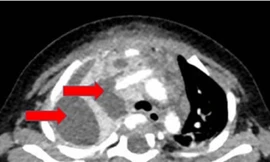

TPO - Bé trai 7 tháng tuổi nhập viện trong tình trạng nguy kịch. Qua xét nghiệm, các bác sĩ xác định, bệnh nhi bị nhiễm khuẩn tụ cầu vàng - loại vi khuẩn được mệnh danh là 'vô địch kháng kháng sinh'.